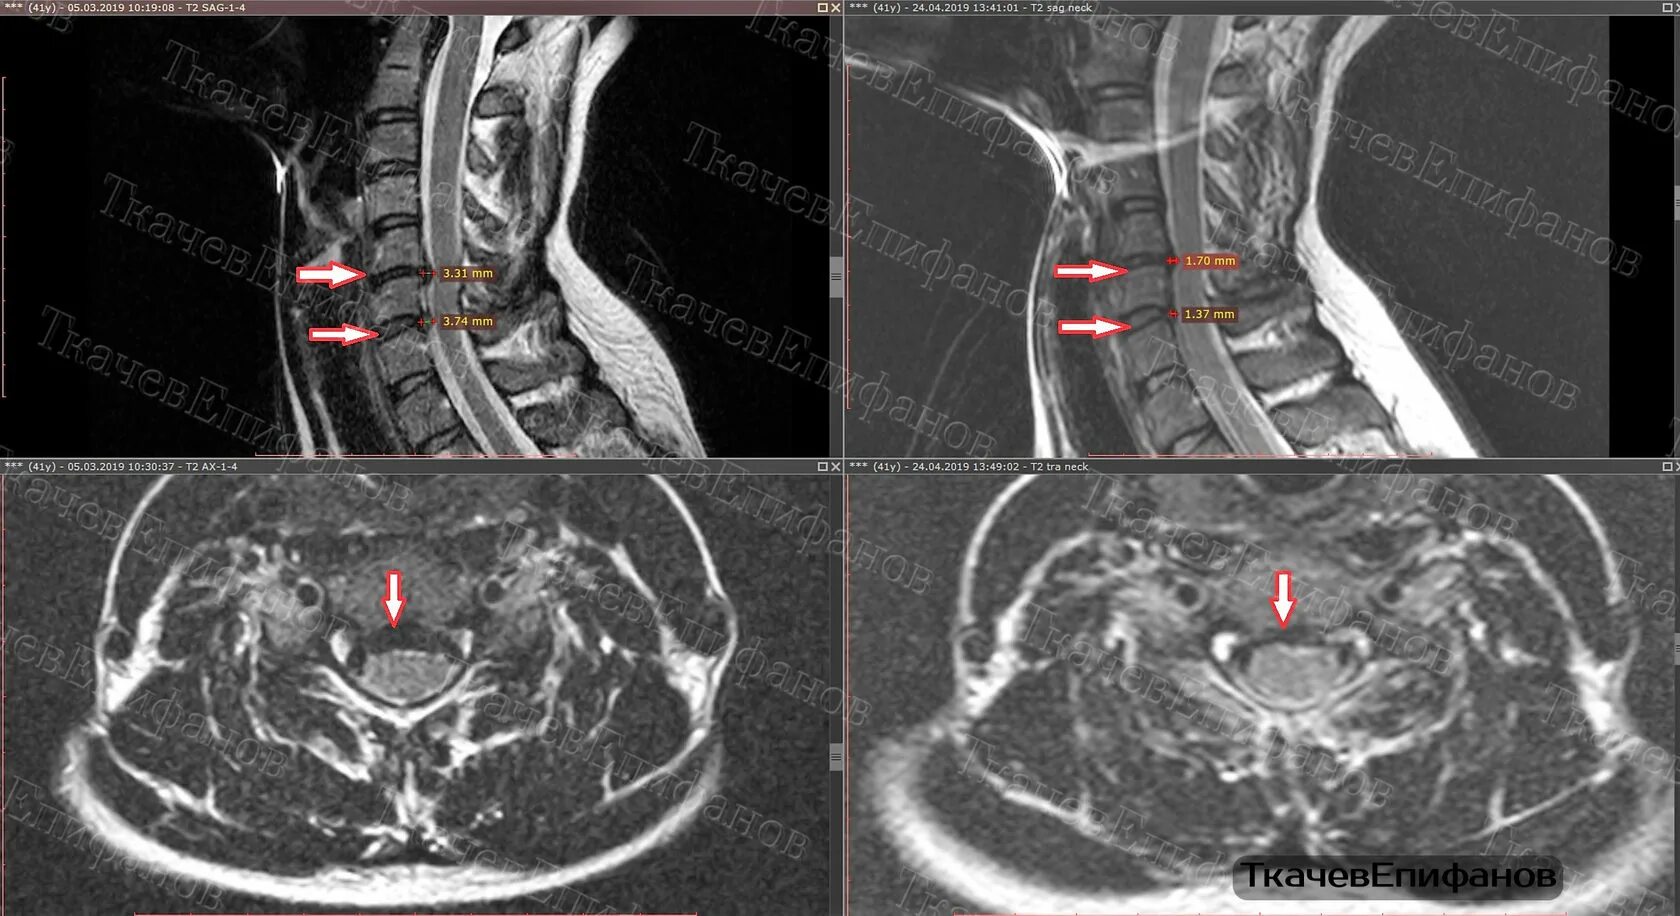

При каких размерах грыжи делают операцию